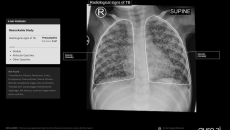

pediatric tuberculosis

Its chest X-ray analysis AI tool is the first to receive Europe's clearance for use in children aged 0-3.